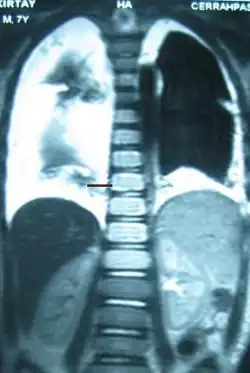

| Diagnostic method | X-ray, CT scan, thoracic MRI, fluid sampling |

The cisterna chyli can be found in a thoracic MRI, making it possible to confirm chylothorax. However, MRI is not the ideal method to scan the thorax, and so it is rarely used. Another diagnostic technique is conventional lymphangiography. It is rarely used since there are equally sensitive yet less invasive techniques available to identify a chylothorax. Lymphangiography procedures use the contrast dye agent lipiodol, which is injected into the lymphatic vessels. The chylothorax shows up on the images and identifies the source any leak in the thoracic duct.[1]